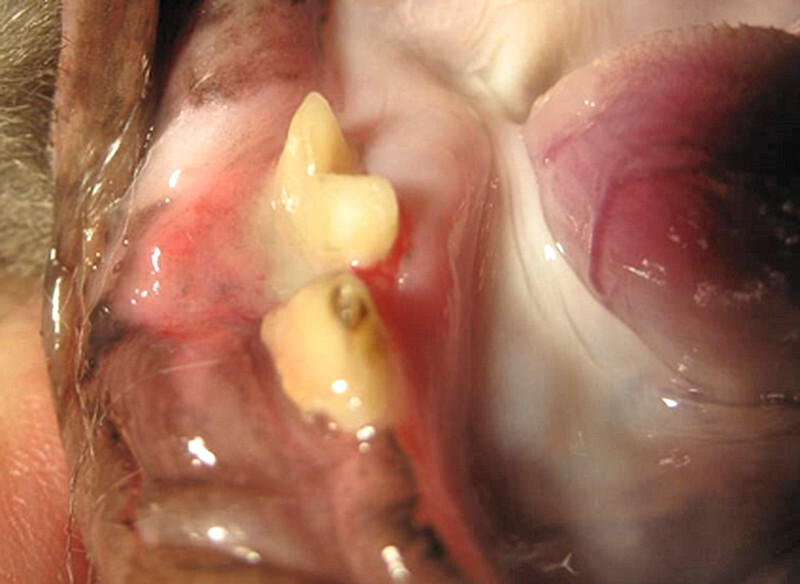

Orale Plattenepithelkarzinome (PEC) können gingival, sublingual und tonsillär lokalisiert sein, wobei die gingivale Form als das häufigste orale PEC der Katze sowohl maxillär als auch mandibular auftritt. Das Wachstum ist infiltrativ und Metastasen finden sich eher selten [6] . Die vorliegende ausgeprägte Osteolyse imponiert meist bereits bei der Diagnosestellung [3] und typischerweise werden beim gingivalen Plattenepithelkarzinom gelockerte Zähne beobachtet. Gerade dann, wenn bei Katzen Zähne gelockert oder „leicht“ zu extrahieren sind, ist besondere Aufmerksamkeit geboten und entsprechende Kieferabschnitte sollten unbedingt röntgenologisch untersucht werden. Begleitende orale Entzündungen können einerseits Tumore maskieren, während andererseits proliferative Entzündungen das Vorliegen eines Tumors vortäuschen können ( [Abb. 1] und [2] ).